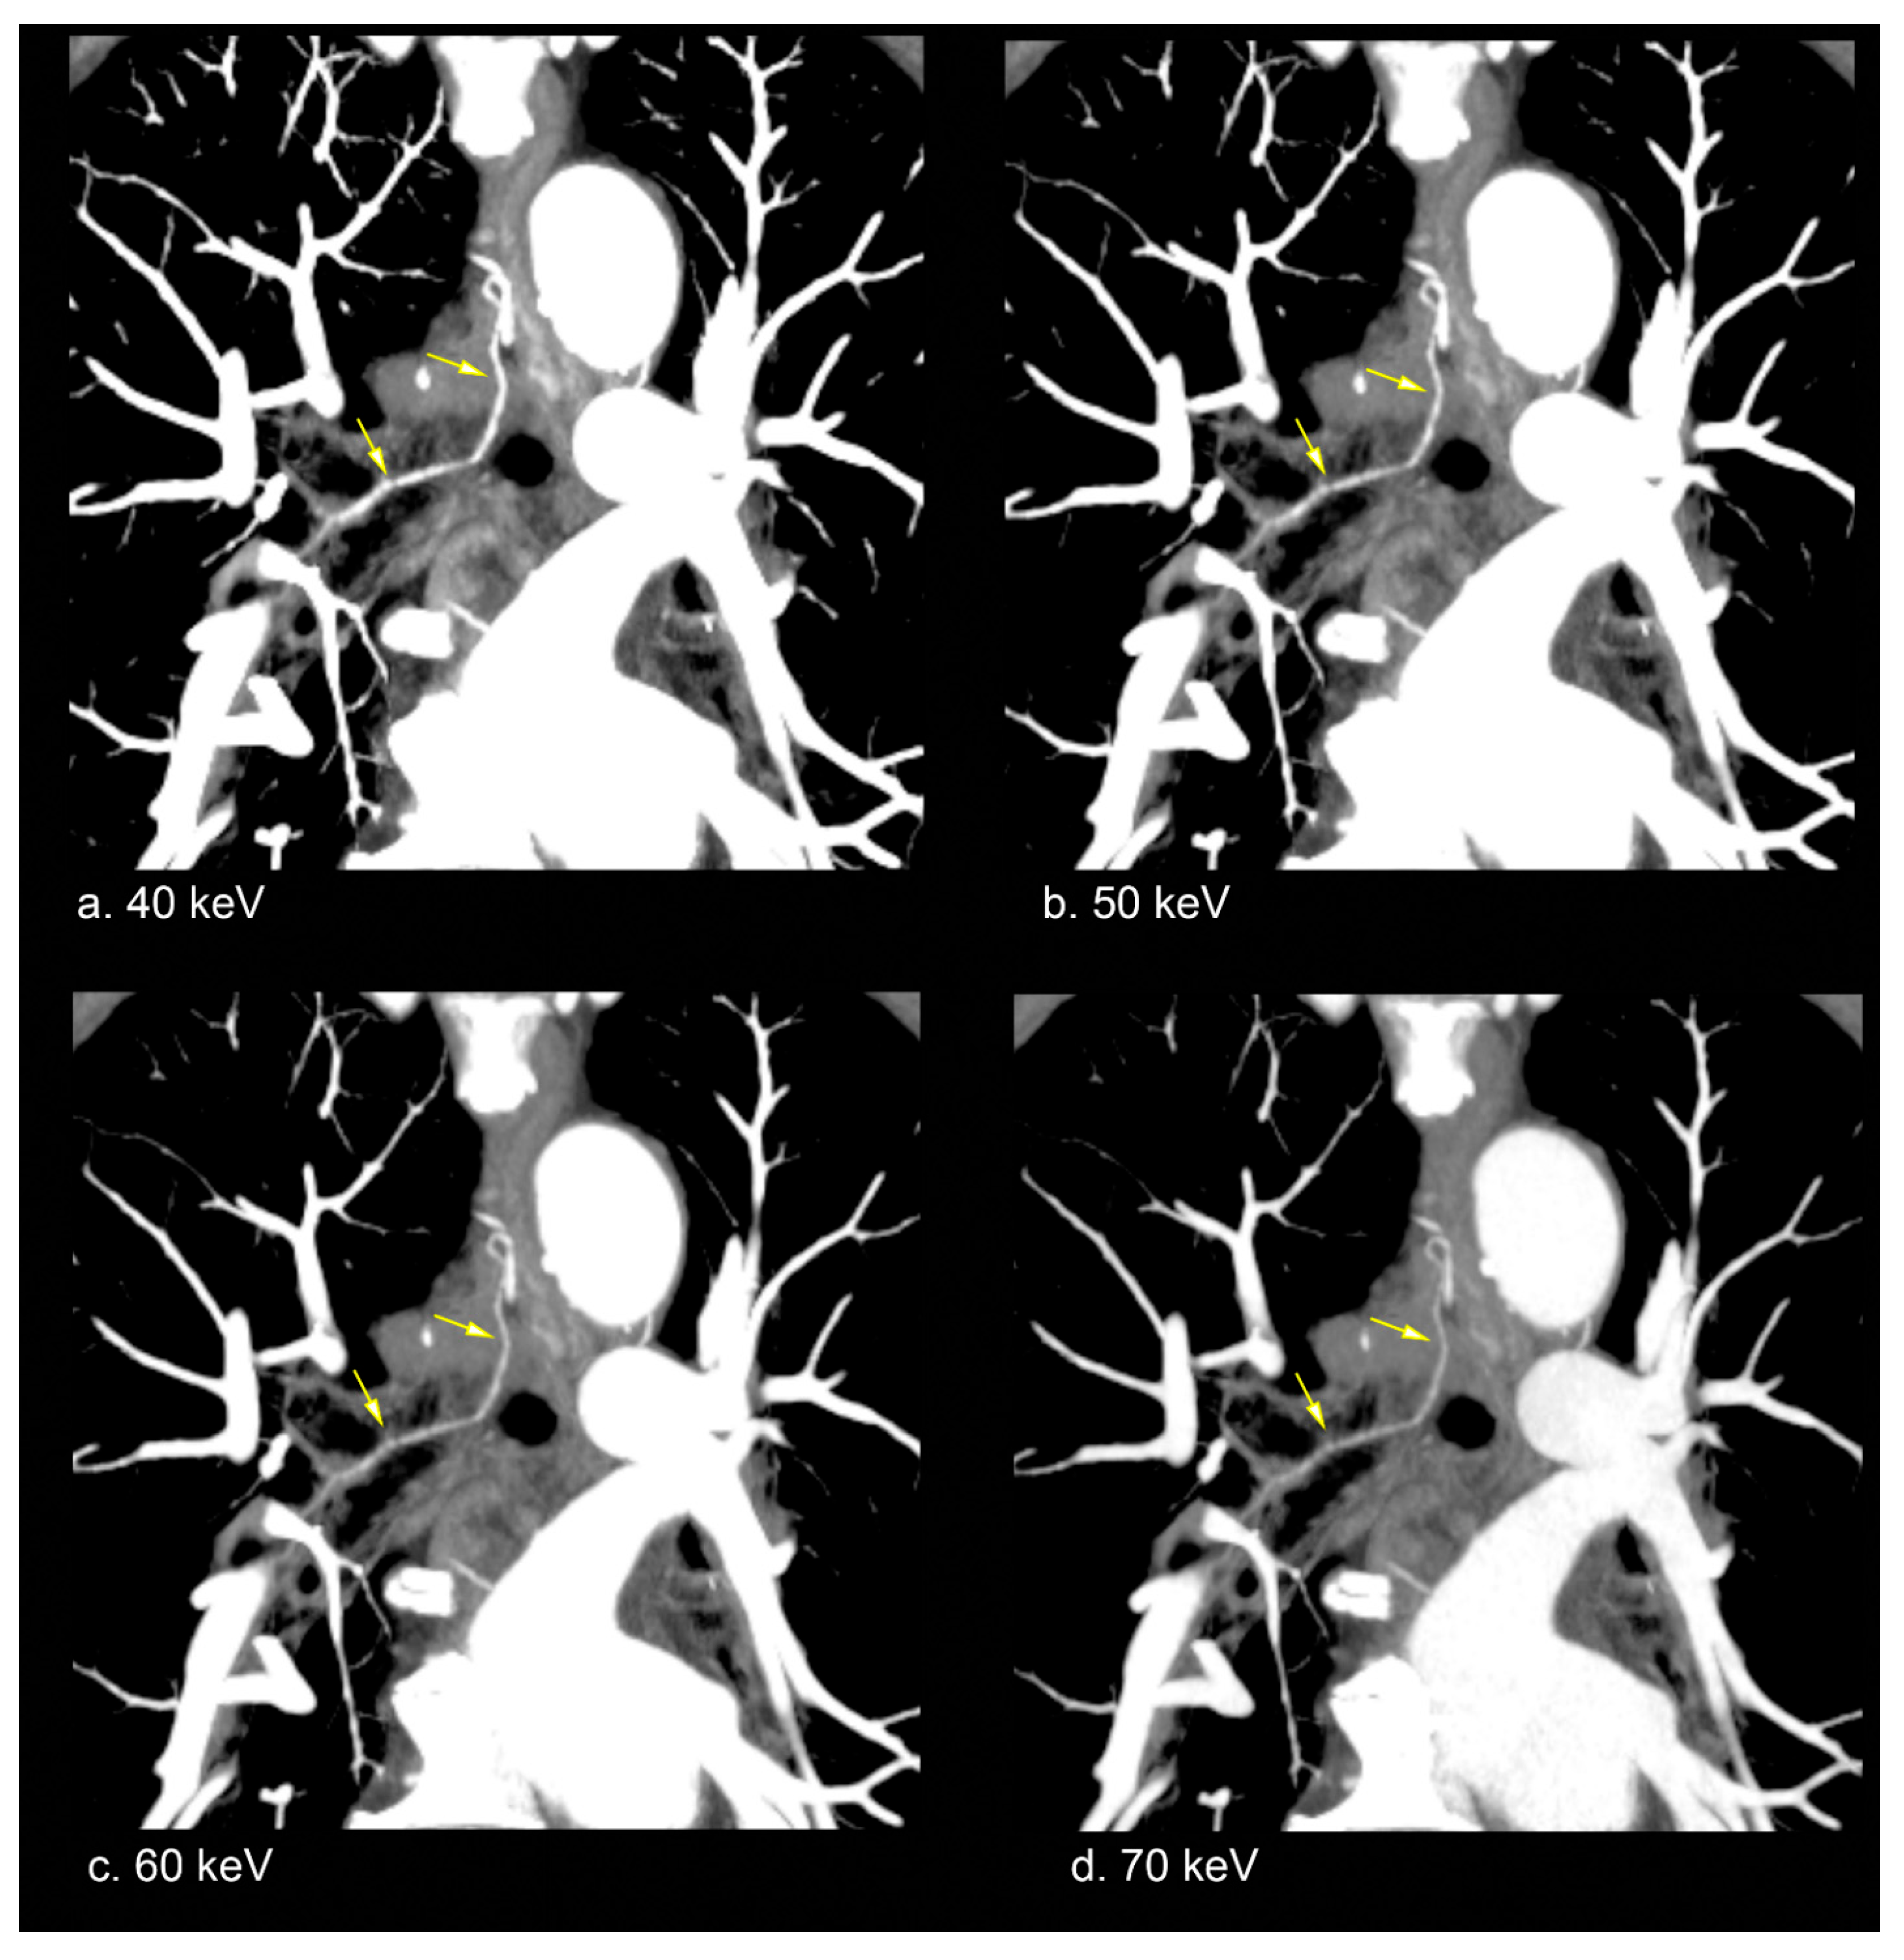

2.5. Representative Image